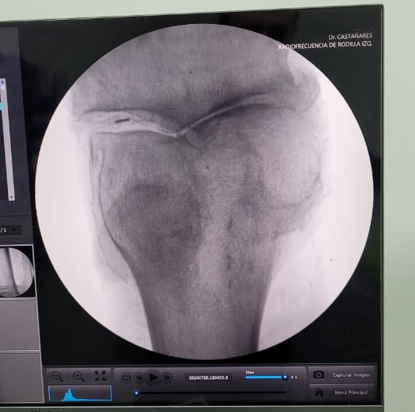

En Tidol tratamos el caso de un paciente de 90 años, con artrosis severa de rodilla izquierda.

El paciente presentaba limitaciones de reemplazo total de rodilla y no se le podía realizar la cirugía por osteoporosis y comorbilidad; por lo que se decidió realizar tratamiento con radiofrecuencia de los nervios geniculados.

Previo al tratamiento, el paciente no podía caminar debido a dolor; luego del tratamiento mejoró notablemente su sintomatología, comenzando a realizar la rehabilitación con fisioterapia dirigida.